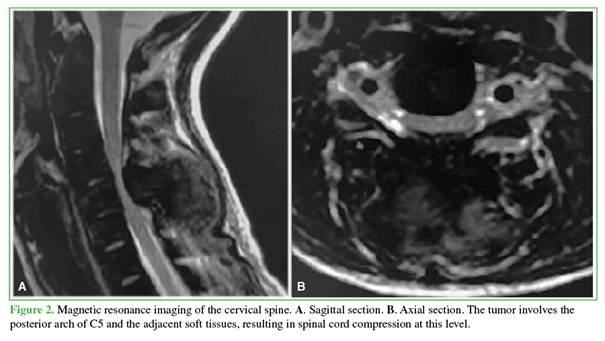

Plain radiographs and computed tomography of the cervical spine demonstrated a large osteolytic lesion with sclerotic margins involving the posterior arch of the fifth cervical vertebra, with extension into the adjacent soft tissues (Figure 1). Magnetic resonance imaging revealed severe spinal cord compression at the level of the fifth cervical vertebra (Figure 2).

Brown tumors typically appear on plain radiographs or computed tomography as lytic, multilobulated lesions that may or may not present peripheral sclerotic margins. On magnetic resonance imaging, these lesions are hypointense on T1-weighted sequences and hyperintense or isointense on T2-weighted sequences, with a tendency to invade adjacent tissues. Intravenous contrast administration usually results in lesion enhancement.7,8

In our patient, the lesion involved the entire posterior arch of C5 and extended not only into the paravertebral soft tissues but also into the posterior epidural space, producing significant spinal cord compression.